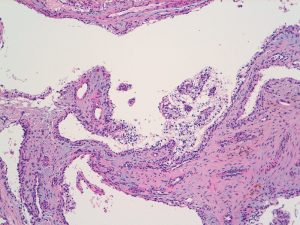

Histological examination showed a partly solid and partly cystic lesion within the paratesticular soft tissue. The cystic spaces showed focal short papillary projections and were lined by cuboidal to columnar epithelial cells with small round nuclei and abundant clear cytoplasm. The supporting stroma was fibrotic. There was no evidence of cellular pleomorphism, mitotic activity or necrosis. The background testicular parenchyma showed seminiferous tubules with active complete spermatogenesis and no evidence of intratubular germ cell neoplasia.

The lesional cells stained positively for AE1/3, PAX8, CK7, EMA, CAIX (cup shaped positivity). They were negative for WT1, inhibin, brachyury, podoplanin, AMACR, CD10, chromogranin A, synaptophysin, S-100 and GFAP.

The overall appearances were those of a clear cell papillary cystadenoma of the epididymis, a benign neoplasm commonly seen in patients with Von Hippel-Lindau Disease as in this case.